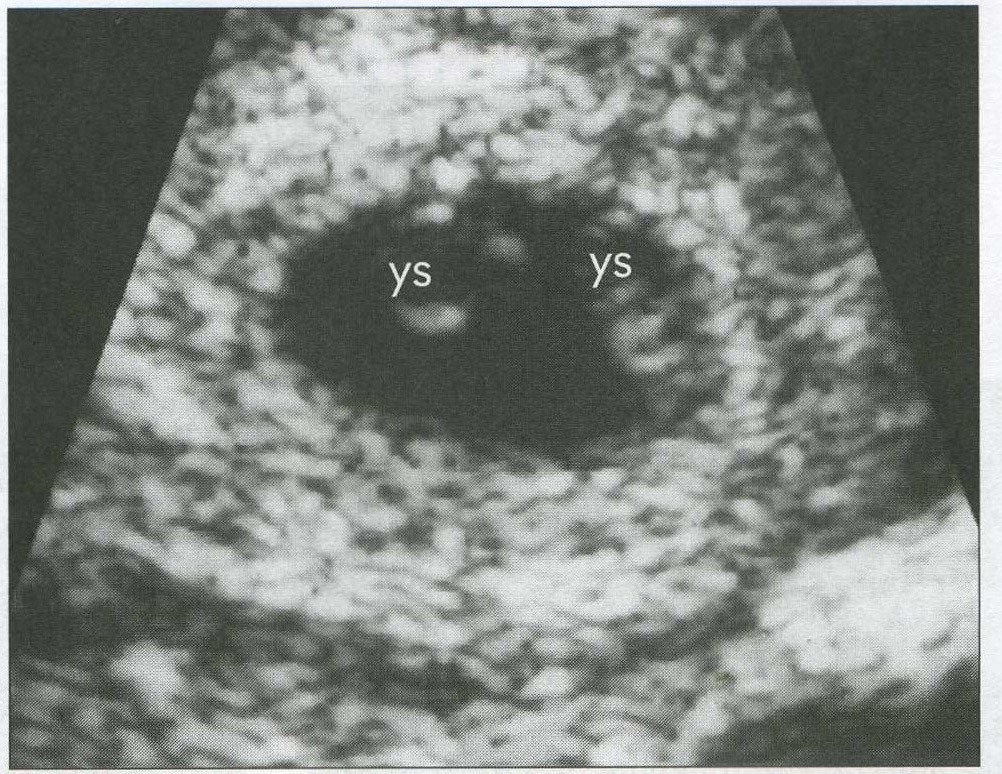

name the type of multiple gestatoins you would predict from this image

dichorionic-diamnionic

name the type of multiple gestations demonstrated by this sonogram

monochorionic -diamnionic